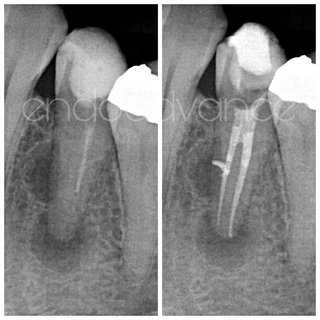

Αρχική ενδοδοντική θεραπεία σε κεντρικό τομέα της άνω γνάθου με δύο ρίζες